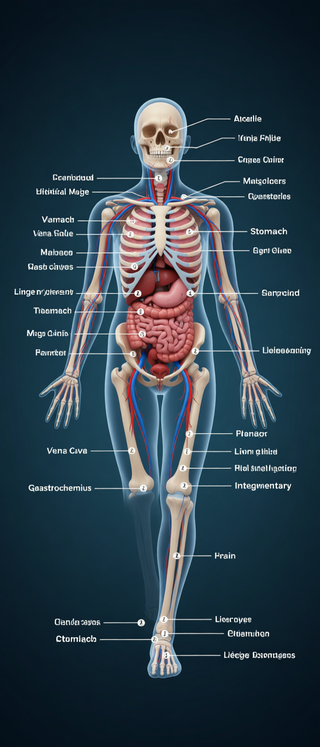

Creates ultra-detailed, multi-layer 3D anatomical visualizations from reference photos.Open

Creates ultra-detailed, multi-layer 3D anatomical visualizations from reference photos.Open

Transform photos into scientific anatomical illustrations.Open

Transform photos into scientific anatomical illustrations.Open